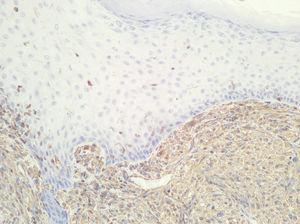

Fig. 2.--Neoformación de estirpe mesenquimatosa constituida por células fusiformes. (Hematoxilina-eosina, x10.)

Neoformación de estirpe mesenquimatosa constituida por células de citoplasma y núcleo fusiforme, dispuestas en áreas y fascículos, entre las que aparecen células multinucleadas de cuerpo extraño (fig. 2), con focos de necrosis y elevada actividad mitótica. Las técnicas inmunohistoquímicas realizadas mostraron negatividad para actina, CD34, HMB45, EMA, CD68, CAM 5.2., desmina, pancitoqueratinas, S-100 y positividad para vimentina (fig. 3).